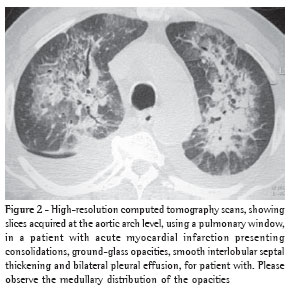

The thickening of the interlobular septa was bilateral in thirteen cases (Figures 1-4) and unilateral in two, also in the patients with fibrosing mediastinitis. In all cases, the thickening was of the smooth type.

Peribronchovascular interstitial thickening was observed in twelve cases (80%), being bilateral in ten (Figure 4) and unilateral in two (the cases of fibrosing mediastinitis).

Septal thickening was not found in isolation. In all patients presenting septal thickening, there were also ground-glass opacities, and the mosaic pattern of attenuation was observed in ten patients (67%). In another study,(9) interlobular septal thickening was also not observed as an isolated tomographic finding, although its presence was closely correlated with peribronchovascular interstitial thickening.

Peribronchovascular interstitial thickening was seen in twelve patients (80%). In ten patients, the thickening was bilateral and smooth. In the two cases of fibrosing mediastinitis, the peribronchovascular interstitial thickening was unilateral. Such thickening is identified by determining the thickness of the bronchial walls. The presence of peribronchovascular interstitial thickening reflects, for hydrostatic edema patients, drainage of the fluid via central interstitial pathways.(3) Em outro estudo,(9) o espessamento foi achado na tomografia computadorizada de alta resolução em quatro de sete pacientes.

In another study,(9) such thickening was detected in the high-resolution computed tomography scans in four of seven patients.